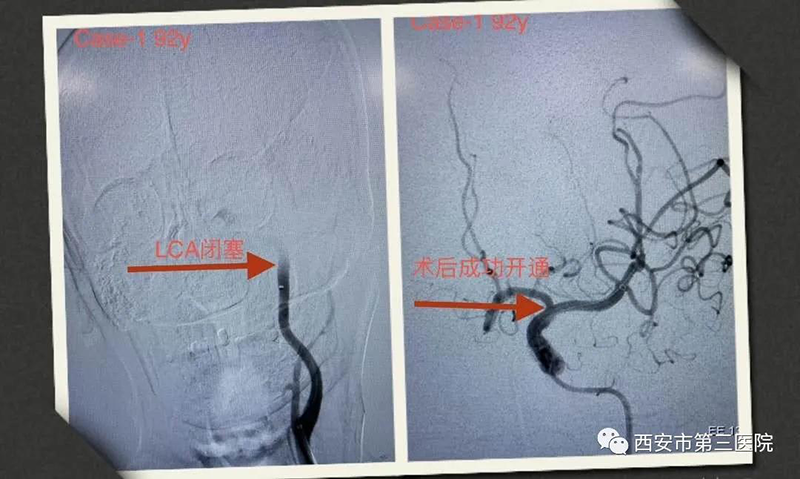

疫情期间大家本就诚惶诚恐,加之高龄老人突然病倒,让全家人都手足无措。市三院急诊接诊后按照相关流程认真排查新冠肺炎,加强防护措施……此刻,时间就是生命,考虑诊断为脑血管,急诊科急请卒中绿色通道韩楠楠主治医师会诊,并立即启动卒中绿色通道,快速有序完成影像学检查;初步诊断:脑梗死,左侧颈内动脉急性闭塞。

患者颈动脉堵塞,血栓负荷大,选取导管抽栓技术结合SWIM支架取栓;从手术开始到闭塞血管完全再通仅仅用了35分钟,大家紧张严肃的脸上露出了笑容。术后,老人由昏迷转为清醒,并和医护人员清晰流利地对话,四肢逐渐活动自如。家属连声感谢。